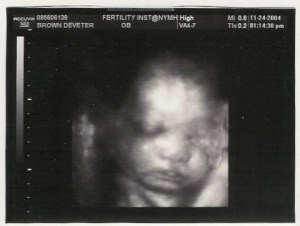

I just read a story on Parent Dish about the Duggar’s giving birth… “Michelle Duggar, star of TLC’s “18 Kids and Counting” gave birth to her 19th child, a girl, Thursday night via emergency C-section, although she wasn’t due to give birth until spring, TMZ reports. Josie Brooklyn Duggar weighed in at 1 lb., 6 ounces.”